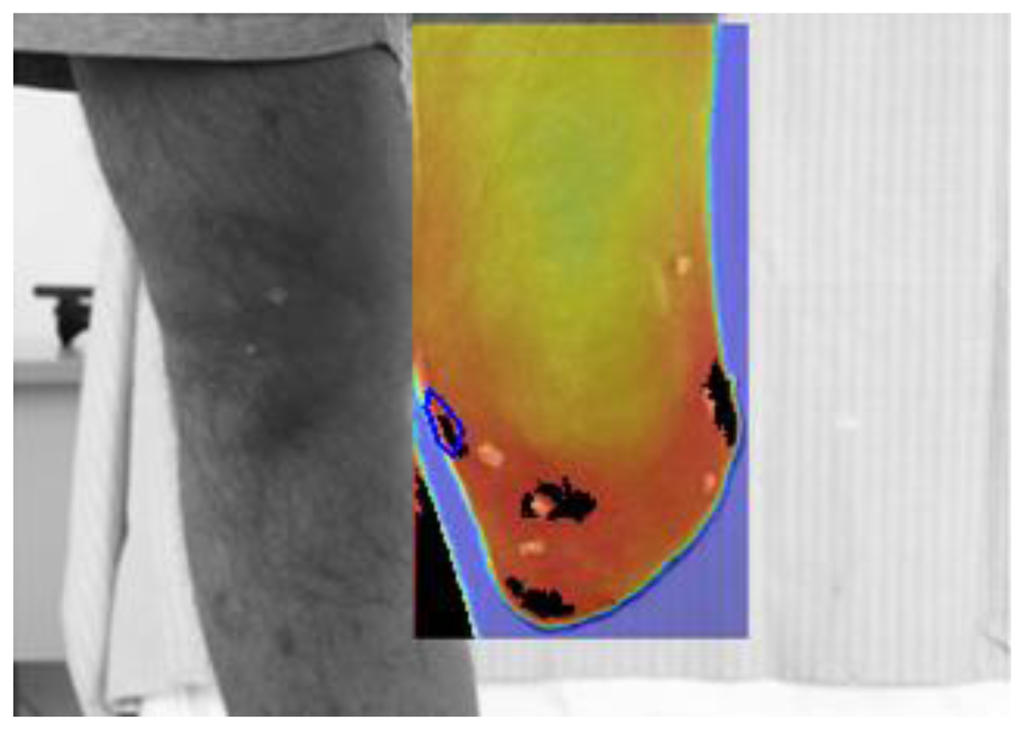

Prosthesis removal (also the liner is removed) and immediate thermal maps and visible image recording (Figure 5);

Regarding step 2, subjects are required to stand up on a spinning platform, with the stump vertical to the platform and aligned with its axis of rotation (Figure 5). Cameras stand on tripods and are not moved for collecting the different anatomical planes; instead the platform is rotated in steps of about 90° so that the whole subject rotates. While collecting basal images, the images collected after walking are used as reference to reposition the subject.

Regarding step 7, a dedicated software for infrared thermal maps analysis and integration with visible images and with the wearable sensors was developed in MATLAB (The Mathworks, Natick, MA, USA). The software implements a projective image-registration algorithm to superimpose “after-walking”, “basal” and visible images (Figure 6). The algorithm takes advantage of tiny ABS markers applied onto the subject's stump as starting guess for subsequent refinements. Then, isothermal images and differential thermal images are obtained for the whole image of specific regions of interest (ROI). The software also reads the Seeeduino data format and plots the time history of sensor recordings.

The thermal imaging results are summarized in Table 5. An average increase of 20% in hot areas is shown after walking. This is consistent and statistically significant (paired t-test, P > 95%). These “possibly critical points” demonstrate good inter-subject repeatability: in 80% of subject they are identified in the inferior patella region and in the medial femoral epicondyle; two other areas are located in the tibial tuberosity area and on the lateral femoral epicondyle in 40% of subjects.